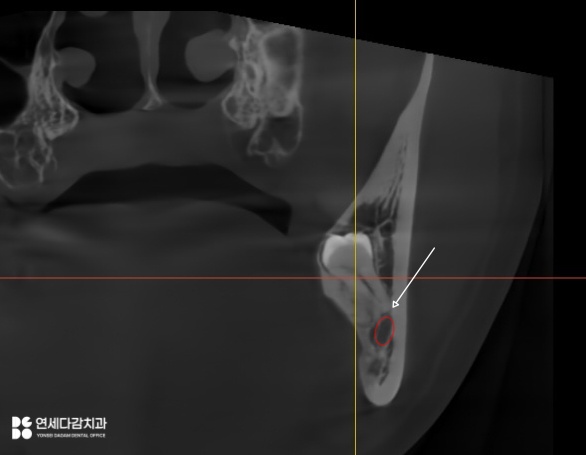

그래서 오금역 치과 에서는

CT 분석이 중요하다고 말씀드립니다.

2025.12.14

이는 2차원적인 엑스레이와는 다르게

입체적으로 치근단과 신경관의 관계를

시각화여 보여주는 장비입니다.

주행 경로를 정확히 파악할 수 있으며,

치아 뿌리의 각도와 방향까지 정확히 보여주어

발치 시 어떻게 분리해야 될지

어떤 방식으로 접근해야 되는지에 대한

섬세한 계획을 세울 수 있습니다.

해당 케이스는 신경관이 치근 끝에 닿아 있어

최소한의 자극으로 진행해야 됩니다.

특히 원심 부위는 잇몸 속에 묻혀 있으므로

절개 후 뼈를 정리하는 과정이 필요합니다.